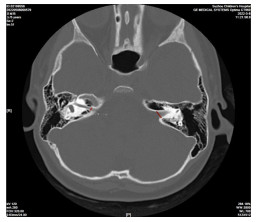

Preoperative HRCT of temporal bone combined with inner ear MRI in patients with cochlear implantation

WU Lin, JIA Huihui, CHEN Mengmeng, GU Wei, WANG Aiping

2026, 24(1): 113-116. doi: 10.16766/j.cnki.issn.1674-4152.004342

43 0

Abstract:

Objective  To address the clinical difficulties of complex anatomical structure and high risk of electrode implantation in children with severe sensorineural deafness during cochlear implantation, and to explore the application value of a combined assessment using high-resolution temporal bone CT (HRCT) and multimodal inner ear MRI before surgery, thereby providing imaging evidence for optimizing surgical planning and reducing the risk of complications.  Methods  A total of 192 children (215 affected ears) with severe or profound sensorineural deafness who underwent surgical CI treatment at the Children' s Hospital Affiliated to Soochow University from January 2021 to December 2024 were selected. All patients underwent temporal bone HRCT and inner ear MRI examinations. The diagnostic efficacy of the two methods for detecting inner ear malformations and abnormal electrode implantation were compared. Univariate and Logistic regression analyses were used to analyze the risk factors associated with abnormal electrode implantation.  Results  Among the 192 cases (215 ears) of children, a total of 140 cases (159 ears) had inner ear developmental malformations, with some unilateral malformed ears presenting with multiple malformations. The detection rate of cochlear malformation identified by inner ear MRI was significantly lower than that by HRCT of the temporal bone (P < 0.05). Transtemporal bone HRCT combined with inner ear MRI examination identified abnormal electrode implantation in 29 ears. Among them, the abnormal implantation rate without inner ear deformity was 5.36% (3/56), which was significantly lower than that in ears with inner ear deformity (16.35%, 26/159, P < 0.05). Logistic multivariate regression analysis showed that increased width of vestibular aqueduct, loss of the labyrinthine segment of the facial nerve canal, greater endolymphatic cyst expansion, elevated intraoperative cerebrospinal fluid pressure level, and older patient age were independent risk factors for abnormal electrode implantation (P < 0.05).  Conclusion  Preoperative temporal bone HRCT combined with inner ear MRI can objectively depict the development and anatomical structure of the inner ear in children. Moreover, the width of vestibular aqueduct, the integrity of the labyrinthine segment of the facial nerve canal, the degree of the endolymphatic sac enlargement, and the intraoperative cerebrospinal fluid pressure are independent risk factors for abnormal electrode implantation.